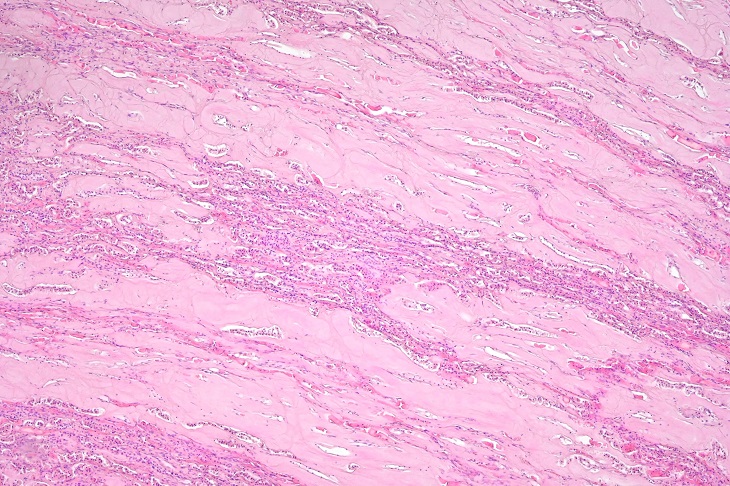

研究チームは日常的に様々な動物の病理検査を進める中で、国内の飼育施設にて19歳で死亡したホワイトライオンにて、腎臓の皮髄境界部への重度のアミロイド沈着を特徴とする全身性アミロイドーシスが生じていることを発見しました。このアミロイド沈着パターンはこれまで報告が無いものだったため、次いで免疫組織化学および質量分析法を用いたプロテオーム解析を実施し、アミロイドの原因がアポC-IIIであることを同定しました。ホワイトライオンにおける本疾患の発生状況を調べるため、過去に死亡した5頭のホワイトライオンを遡って再検査したところ、0.5歳と10歳の個体は陰性でしたが、19~21歳のホワイトライオン3頭が同じ病態を発症していました。